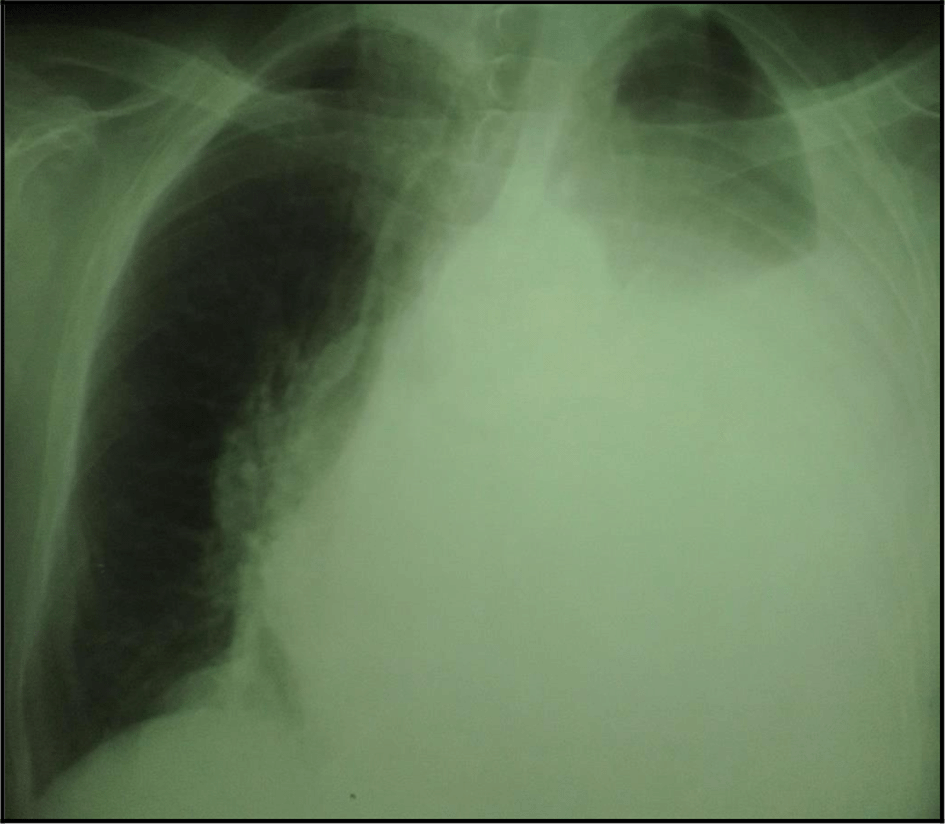

The chest X-ray showed left pleural opacity with signs of compression (Figure 1). So, an exploratory and evacuating ultrasound-guided pleural puncture was immediately performed. The thoracic ultrasound showed a massive anechoic, free left pleural effusion associated with pleural nodules (Figure 2). Analysis of the pleural fluid showed a serohaematic exudative fluid with a predominantly lymphocyte formula (80%). A Gram stain fast bacilli (AFB) stain and bacterial and tuberculosis cultures for were all negative. Therefore, a malignant origin was suspected. The chest CT-scan revealed a left-sided malignant pleural effusion associated with mediastinal adenopathy, extended secondary bone lesions and subcutaneous lesions (Figure 3). Additionally, the echocardiography was normal.